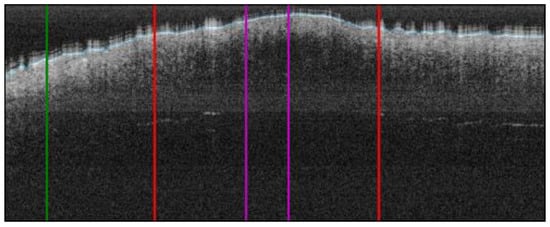

| Melanoma in-situ (MIS) Case 1 | Localization: right abdomen |

![]() | ![]() |

| Melanoma in-situ (MIS) Case 2 | Localization: left chest |